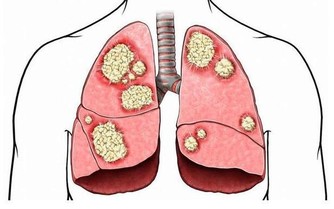

脂肪肝已成為人類第一大肝病

目前,世界各地的脂肪肝的發病率逐年上升,發病年齡也越來越小。它可能發生於各個年齡段,以40-50歲最為常見。酒精性脂肪肝男性患者居多,非酒精性脂肪肝過去認為以女性為主,近年來認為男女發病率幾乎相當。在發達城市,成人脂肪肝的患病率更是超過了30%,主要病因就是營養過剩和酗酒,所以脂肪肝又被稱為「富貴病」。而在一些貧窮地區,由於蛋白質、熱量攝入不足也會引起脂肪肝。通過上文所知,脂肪肝不只是胖子的專利,瘦人也可發生。